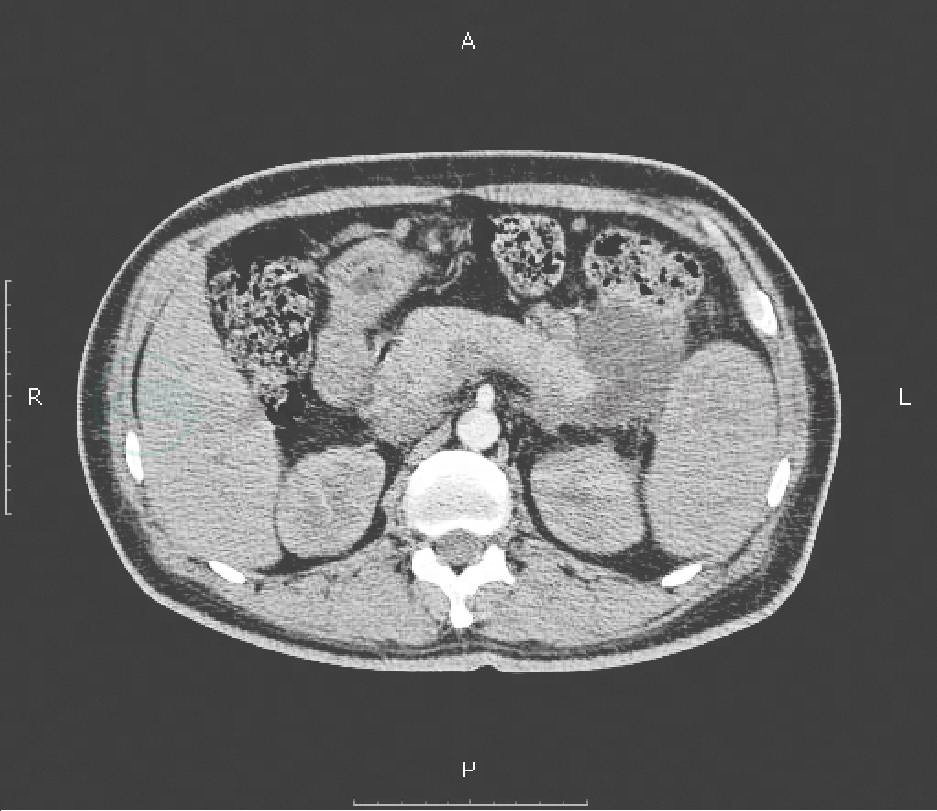

腹部CT平扫+增强:胰尾部囊性低密度影,考虑胰腺假性囊肿(图1),胃底静脉轻度曲张,脾脏肿大。

图1 CT示胰尾部假性囊肿